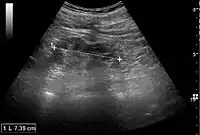

Figure 24. Chronic pyelonephritis with reduced kidney size and focal cortical thinning. Measurement of kidney length on the US image is illustrated by ‘+’ and a dashed line.[1]